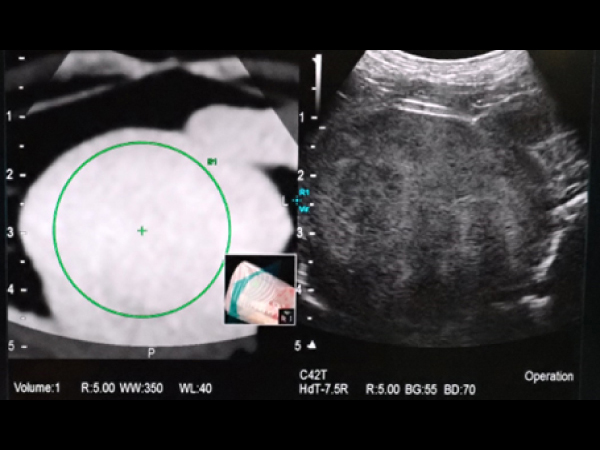

内側左葉に36.2×45.1㎜の腫瘤が認められ、ツルーカット生検で肝細胞癌と診断されました。 摘出も可能でしたがもともと肝臓が小さく肝機能が低下しているため負担の少なさを考慮してフュージョンイメージングを用いてアブレーションを実施しました。 症例②と同様に肝臓腫瘍の周囲に生理食塩水を満たして実施しました。 術後は合併症もなく翌日元気に退院しました。摘出手術を行うよりも麻酔時間の短縮や術後の経過が良好でした。

フュージョンイメージング

アブレーションする範囲を緑丸のようにガイドをつけることも可能

フュージョンイメージングのガイドを用いてアブレーションを実施

アンテナ(青矢頭)と焼灼されているところ(赤丸)

アブレーション後の超音波画像